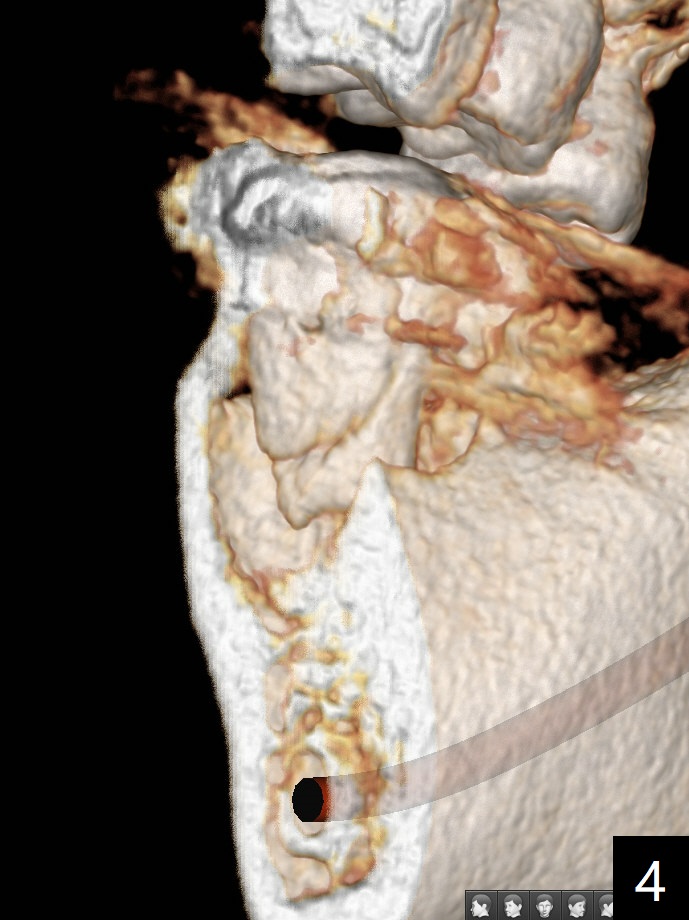

Mesial Root Fracture

A 35-year-old man has repeated pain at #18 (Fig.1). He is a bruxer with exostosis (Fig.2 *). It appears that the mesial root of the affected tooth has vertical fracture (Fig.1-4). A 5x11.5 or 13 mm implant is appropriate (11 or 13 mm FC, Fig.5). Draw blood for PRFx2/sticky bone.